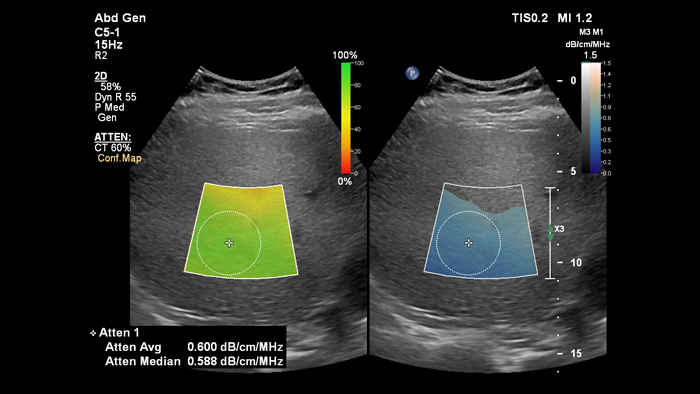

A imagiologia de atenuação pode medir a quantidade de gordura presente no fígado ao calcular o coeficiente de atenuação do som absorvido pelo parênquima hepático. Este método proporciona parâmetros quantitativos de atenuação que podem ajudar os médicos na gestão de pacientes com esteatose hepática.

Imagiologia de atenuação